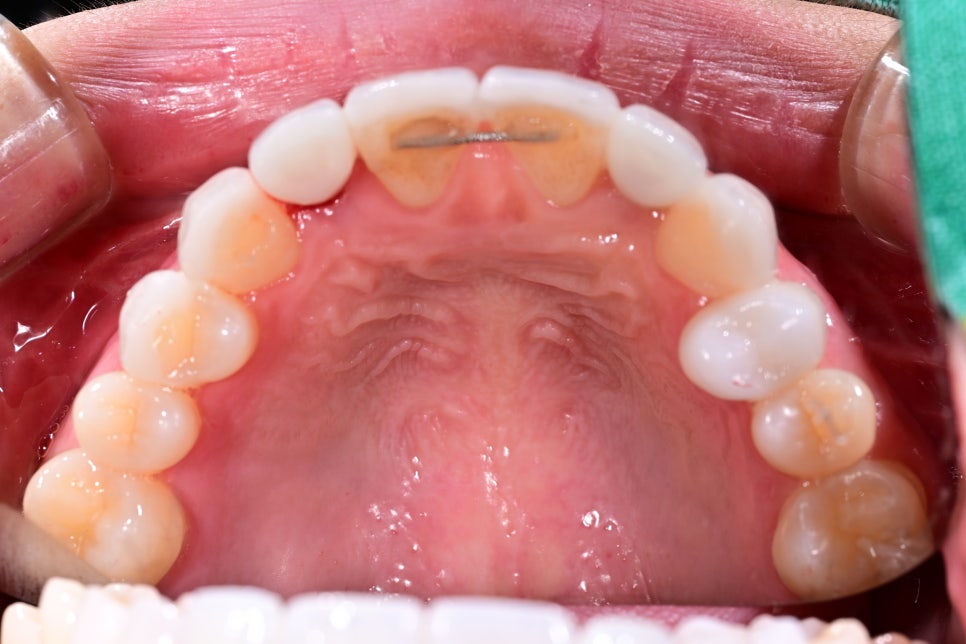

어떤 게 임플란트일까요?

특히 임플란트는 식립해놓은 보철물이 내려가거나 잇몸과의 경계가 깔끔하게 들어맞지 않으면 티가 굉장히 많이 납니다.

실제로 앞니 심미치료에서는 단순히 치아 색만 맞춘다고 자연스러워지는 것이 아니라, 치아의 폭경, 길이, 라인, 표면 질감, 잇몸과의 조화, 좌우 대칭감까지 함께 고려해야 만족도 높은 결과가 나옵니다.

앞니 임플란트는 자연치와 달리 빛 투과감이나 잇몸과의 연결감에서 차이가 나기 쉬워 보철 디자인이 매우 중요합니다.

기존 보철의 색감과 형태, 조화도를 다시 점검하여 주변 치아와 보다 자연스럽게 이어지도록 보철을 재설계했습니다.

앞니 임플란트가 어색해 보이는 이유는?

앞니 임플란트가 부자연스러워 보이는 원인은 꽤나 다양합니다.

-

주변 치아와 맞지 않는 색상

앞니 폭경과 길이 비율의 불균형

표면 질감 차이

잇몸 라인의 미세한 비대칭

인접 치아와의 연결감 부족

기존 보철의 두께감이나 형태 문제

이런 경우 단순히 보철 하나만 바꾸는 것으로 해결되지 않고, 주변 자연치와의 조화를 함께 봐야 더 좋은 결과를 얻을 수 있습니다. 그래서 이번 케이스처럼 라미네이트와 임플란트 보철을 함께 설계하는 접근이 매우 중요할 수 있습니다.